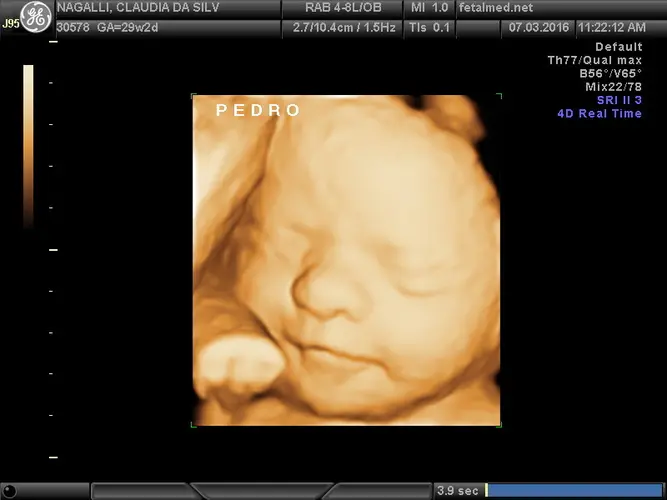

Seu bebê atingiu um marco importante: já pesa aproximadamente 1 quilo e 200 gramas! Com cerca de 38 centímetros da cabeça aos pés, ele está ganhando peso rapidamente e seu corpo está ficando mais rechonchudo e proporcional. As sobrancelhas e cílios estão completamente formados, enquanto os cabelos continuam a crescer e engrossar.

Uma das habilidades mais encantadoras que seu bebê desenvolve nesta semana é a capacidade de piscar. As pálpebras estão completamente formadas e funcionais, e os olhos já conseguem se mover sob as pálpebras. Somado a outros comportamentos já dominados como tossir, chupar o dedo, soluçar e fazer movimentos respiratórios de treino, o piscar demonstra o amadurecimento contínuo do sistema nervoso.

O desenvolvimento neurológico avança significativamente nesta fase. Seu bebê começou a experimentar o sono REM (Rapid Eye Movement), o que significa que provavelmente já está sonhando! O tônus muscular continua melhorando gradualmente, permitindo movimentos mais coordenados e intencionais. Você pode notar que os movimentos fetais estão mais organizados e menos aleatórios do que nas semanas anteriores.

Os pulmões estão quase completamente maduros, embora ainda precisem de algumas semanas para atingir a maturidade total. Os movimentos respiratórios de treino são frequentes e podem ser observados durante exames de ultrassom. É importante lembrar que, apesar desses movimentos, não há troca gasosa real nos pulmões – todo o oxigênio necessário ainda vem através da placenta.